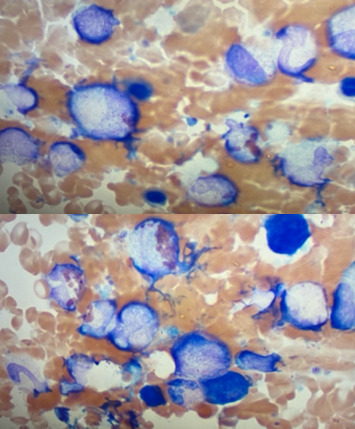

Abstract Image